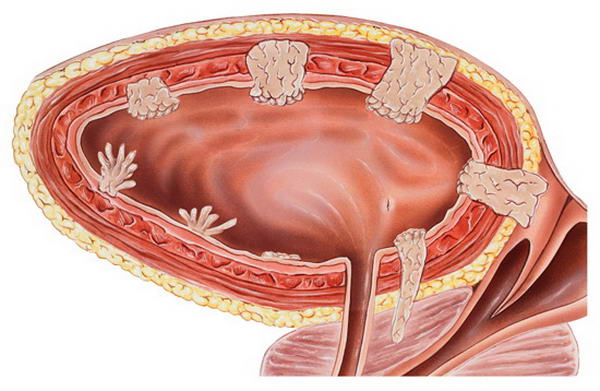

Ung thư bàng quang là gì?

Bàng quang là cơ quan hình quả bóng nằm trong vùng xương chậu, chứa nước tiểu. Ung thư bàng quang là loại ung thư xuất phát từ các tế bào lót bên trong bàng quang, có thể xảy ra ở mọi lứa tuổi nhưng thường gặp nhất ở người lớn tuổi.

Hầu hết ung thư bàng quang được chẩn đoán ở giai đoạn sớm, khi cơ hội điều trị khỏi bệnh rất cao. Tuy nhiên, ngay cả ở giai đoạn sớm, bệnh vẫn có thể tái phát. Do đó, sau điều trị, bệnh nhân ung thư bàng quang thường được theo dõi trong nhiều năm để phát hiện tái phát kịp thời. Phẫu thuật cắt bỏ tuyến tiền liệt bằng laser